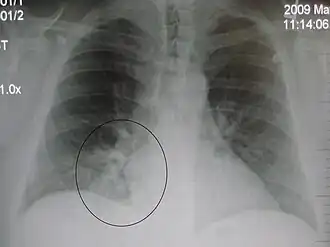

| A chest X-ray showing a very prominent wedge-shape bacterial pneumonia in the right lung | |

Right upper lobe pneumonia as marked by the circle. -